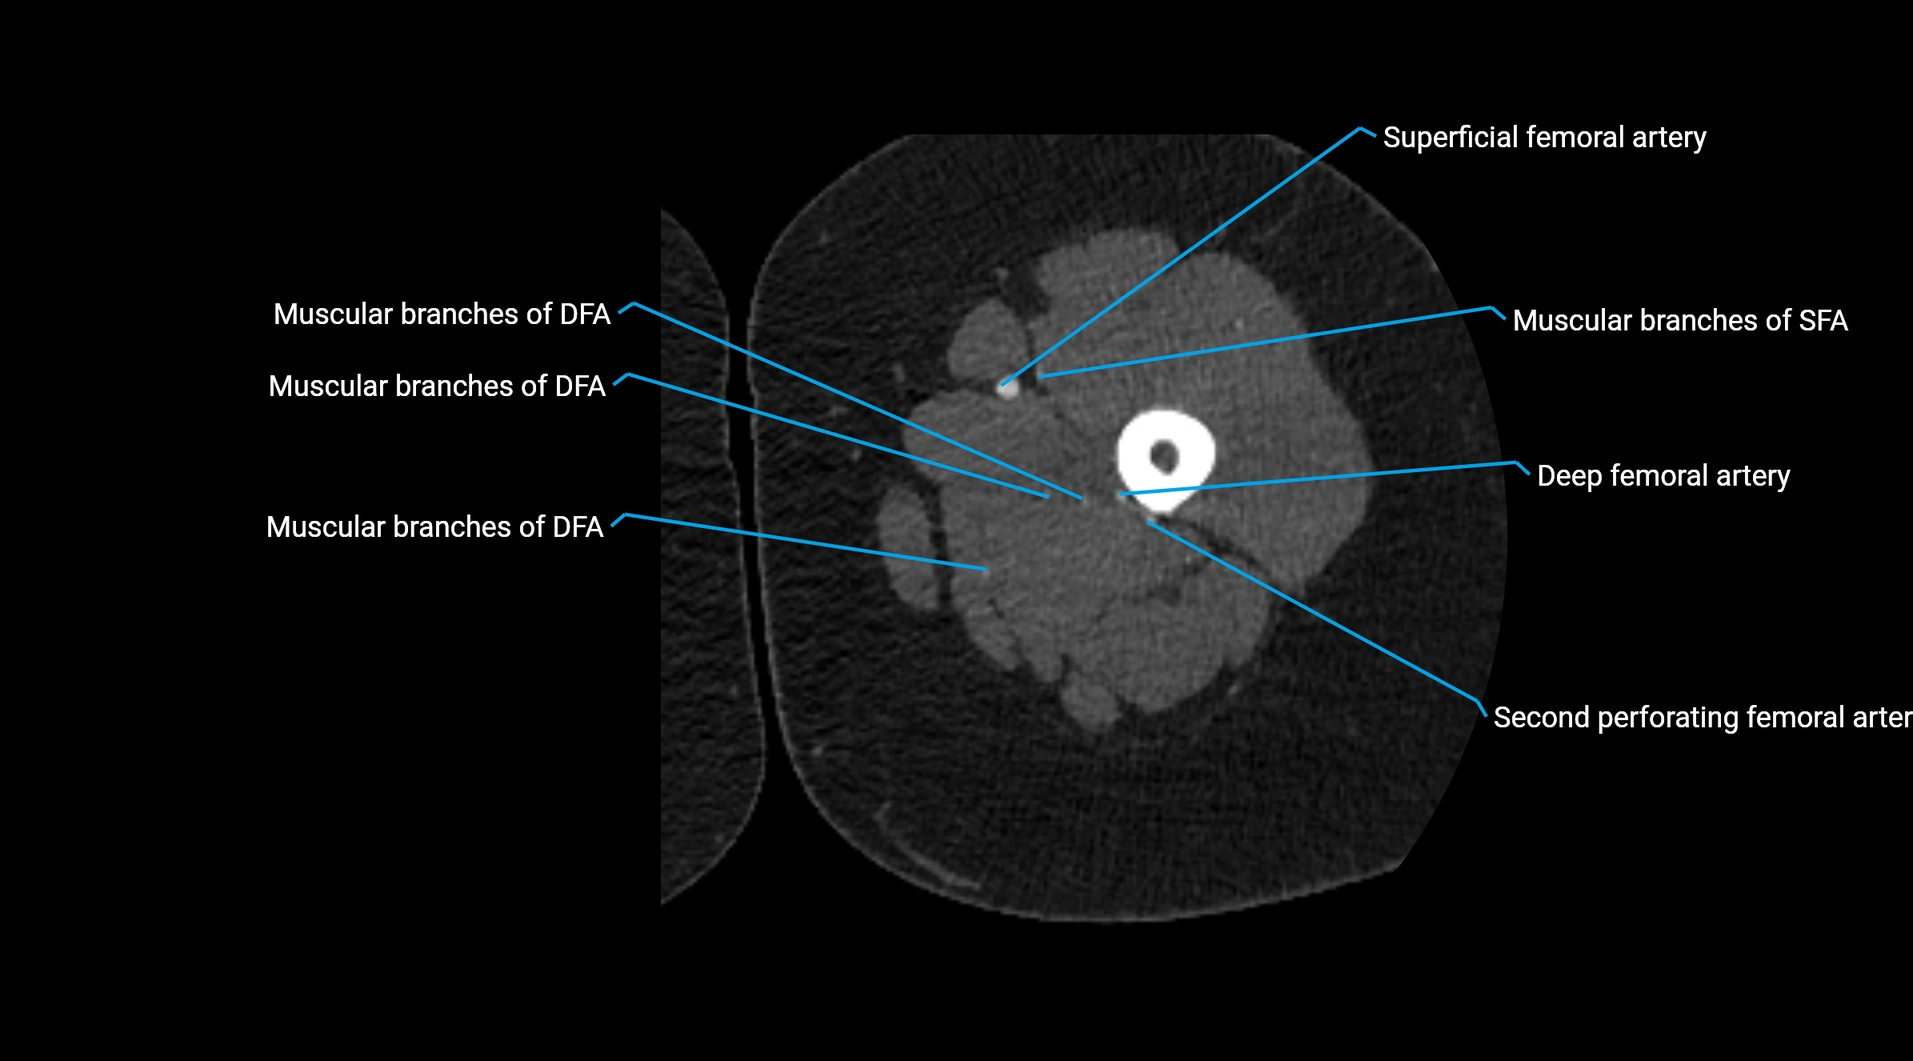

CT images

image